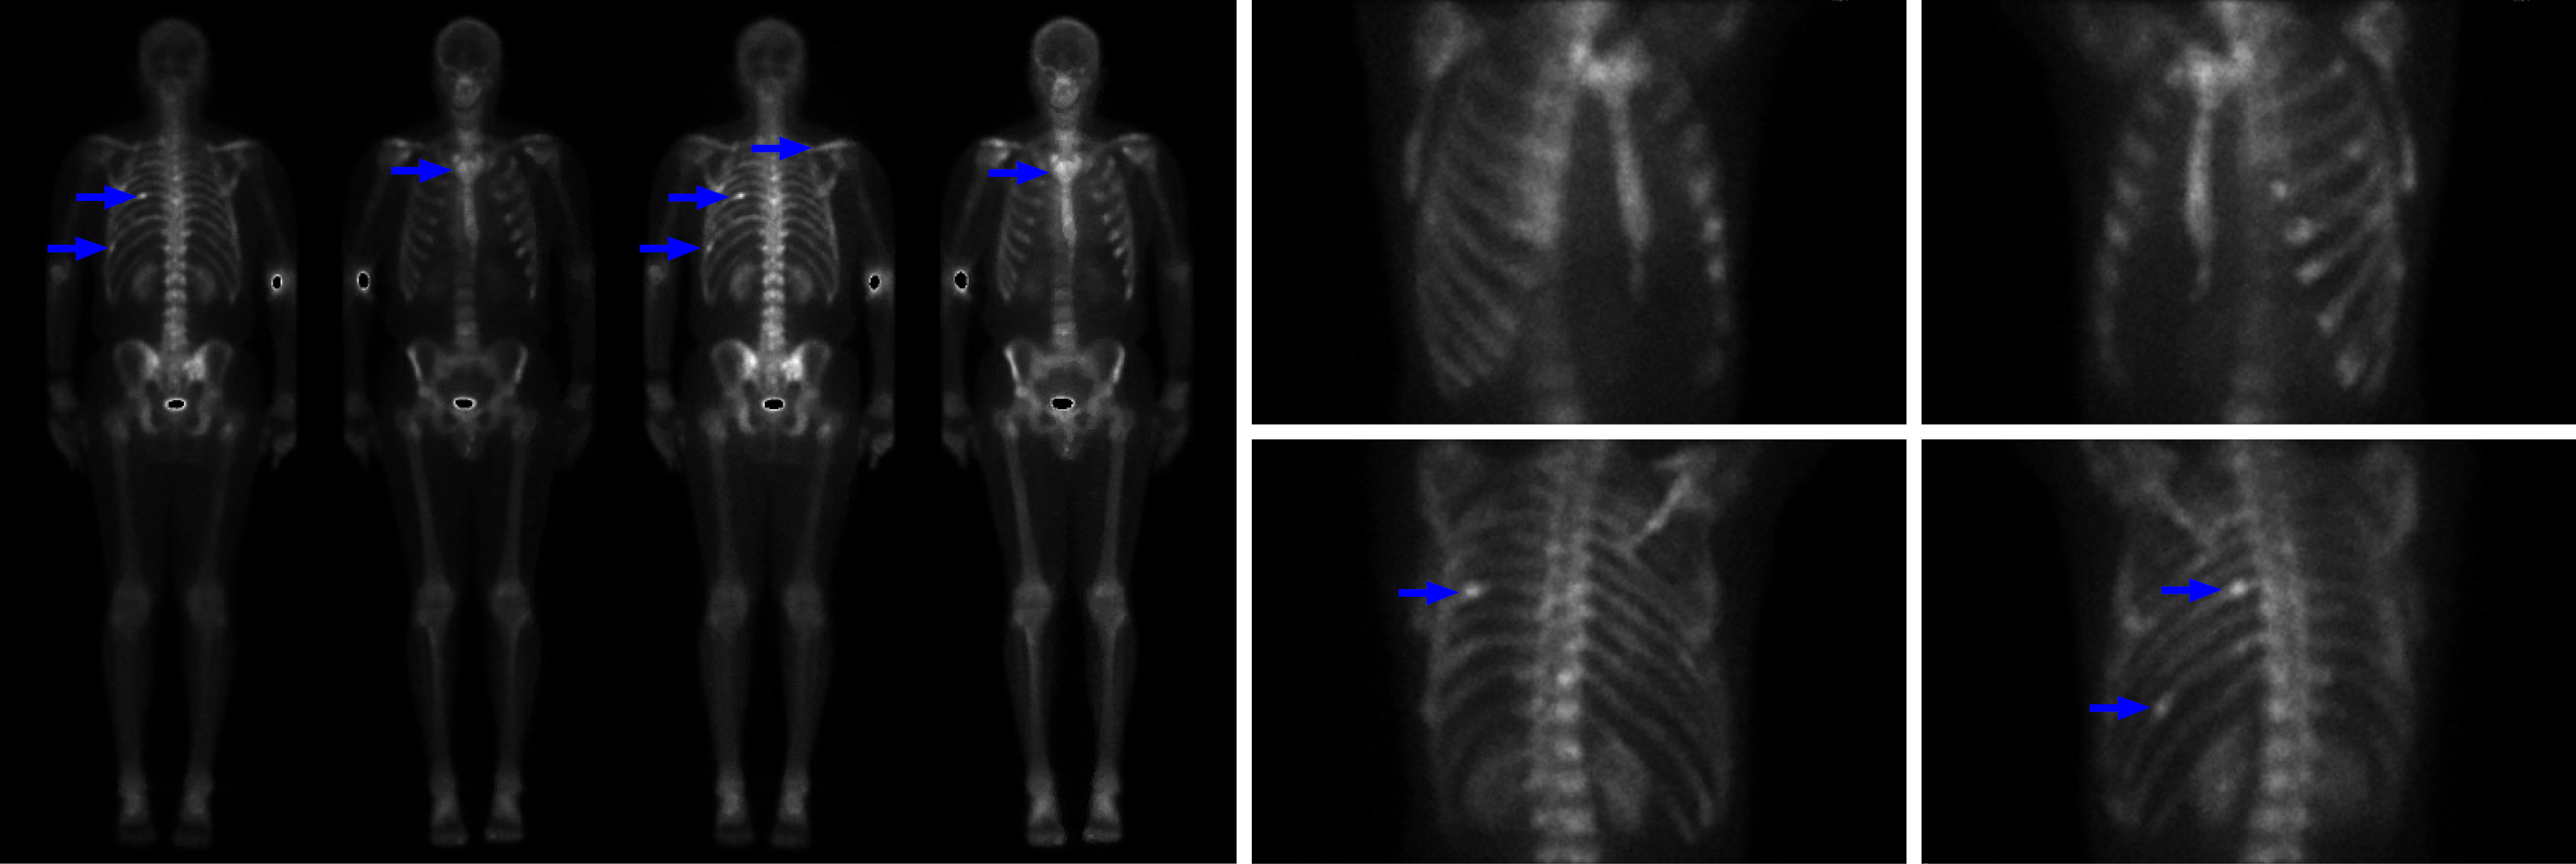

Figure 1 Nuclear medicine whole body positron emission tomography scan.

Extensive abnormal heterogeneous bone remodelling in the axial skeleton, suspicious for multiple osseous metastases. Heterogeneous radiotracer activity (blue arrows) involving multiple ribs, scapula, multiple levels of thoracic spine and right manubrium.